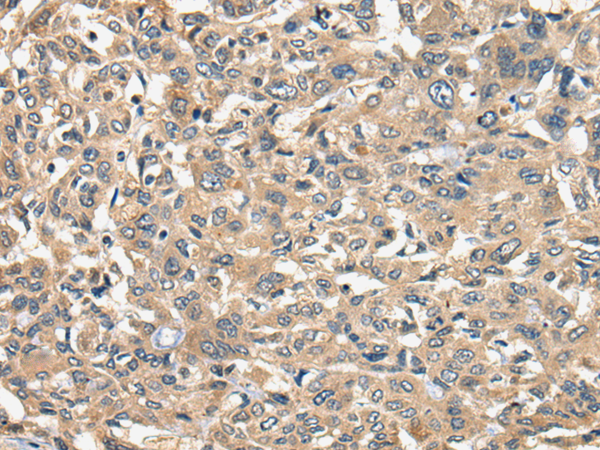

IHC positive control: |

Human liver cancer and Human ovarian cancer |

IHC Recommend dilution: |

25-100 |